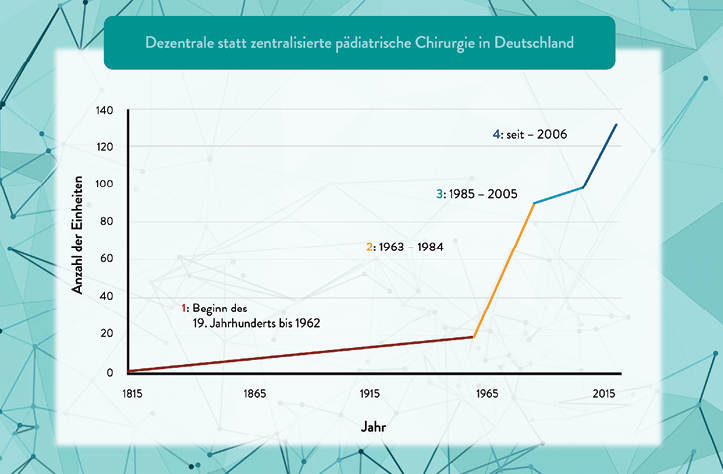

Kinderchirurgie ist ein verhältnismäßig junges Fachgebiet. Zwar wurde die Deutsche Gesellschaft für Kinderchirurgie bereits 1963 gegründet (seit 2024 umbenannt in Deutsche Gesellschaft für Kinder- und Jugendchirurgie, DGKJCH), erst 1992 wurde jedoch auch in Westdeutschland die (in der DDR seit 1955 existierende) Facharztweiterbildung „Kinderchirurgie“ eingeführt [1, 2]. Bis dahin führten Erwachsenenchirurg:innen ohne eine gesonderte Facharztbezeichnung die chirurgischen Eingriffe bei Kindern durch. Die bundesweite Anerkennung von Kindern als besondere Patientengruppe im Jahr 1992 und eine auf sie zugeschnittene Facharztweiterbildung ist als Errungenschaft anzusehen.

Ein Grund für diese hochgradig zersplitterte Versorgungslandschaft mit nahezu ausschließlicher Gelegenheitschirurgie bei Korrekturoperationen von Fehlbildungen ergab sich aus einer wirtschaftlich motivierten Reaktion der Versorgungslandschaft auf die Einführung der Qualitätssicherungsrichtlinie für Früh- und Reifgeborene (QFR-RL) durch den G-BA im Jahre 2006 [12]. Mit dem Ziel, die Versorgung von Früh- und Reifgeborenen sicherer zu gestalten, sieht die QFR-RL u. a. vor, dass in Perinatalzentren des Level 1 und 2 eine kinderchirurgische Versorgung in Rufbereitschaft permanent gewährleistet ist. An die Expertise dieser kinderchirurgischen Rufbereitschaft werden indes keine weiteren Anforderungen gestellt. In Folge dieser Vorgabe stieg seit 2006 konsekutiv die Anzahl Standorte mit einer „Kinderchirurgie“ von vorher 90 auf 156 im Jahre 2024. Dabei sind die Abteilungsmodelle sehr unterschiedlich: es gibt aktuell ca. 90 kinderchirurgische Fachabteilungen, 40 angestellte Kinderchirurg:innen in Pädiatrie und Allgemeinchirurgie, und sechs belegärztliche Konstellationen [13].

Abb. 1: Schmedding A, Rolle U. Decentralized Rather than Centralized Pediatric Surgery Care in Germany. Eur J Pediatr Surg. 2017 Oct;27(5):399–406. doi: 10.1055/s-0037-1607026